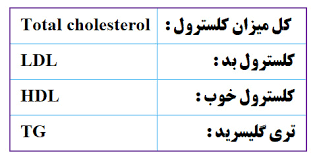

قیمت: 108٬000 تومان - دسته بندی فایل: پاورپوینتپاورپوینت تفسیر کامل برگه آزمایش خون

فروش ویژه پاورپوینت حرفه ای ساقه مغز با تخفیف استثنایی فقط 128 هزار تومان تعداد اسلاید: 70